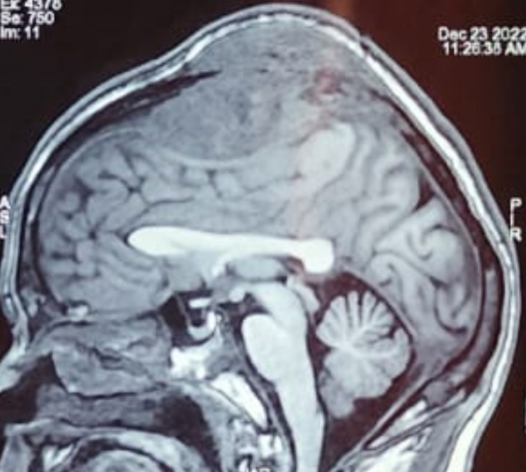

A 30-year-old woman, 3 months post-partum, is admitted after 10 days of headache, vomiting, dizziness and impaired consciousness. She suffers a generalized seizure and requires intubation. Labs show leukocytosis with low CRP. Blood cultures are negative. What would you consider?

A 30-year-old woman, 3 months post-partum, is admitted after 10 days of headache, vomiting, dizziness and impaired consciousness. She suffers a generalized seizure and requires intubation. Labs show leukocytosis with low CRP. Blood cultures are negative.

What would you consider?